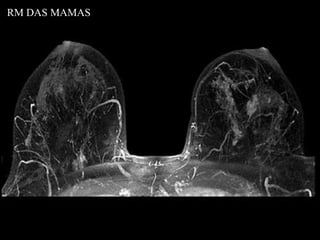

RM DAS MAMAS